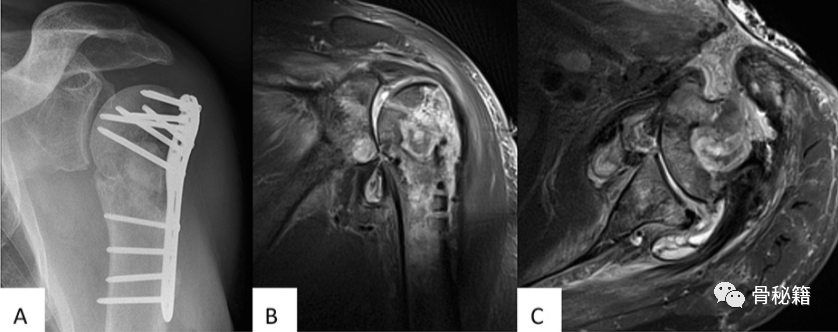

肱骨骨折术后感染,MRI显示感染范围与窦道坏死区域。